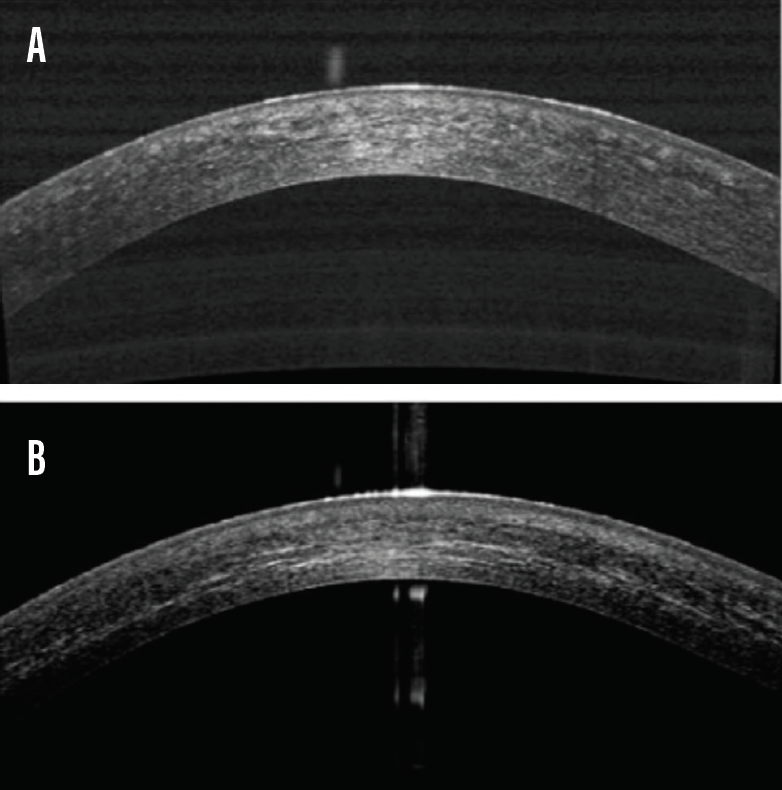

From www.researchgate.net

Representative case of a patient with keratoconus treated with deep Keratoconus Updates this article provides an updated review on the definition, epidemiology, histopathology, aetiology and pathogenesis, clinical. keratoconus (kcn) is a common corneal degeneration characterized by progressive, noninflammatory changes in collagen structure that. this topic last updated: The present article provides an updated review of keratoconus and expands on areas of recently acquired knowledge. a family history of. Keratoconus Updates.